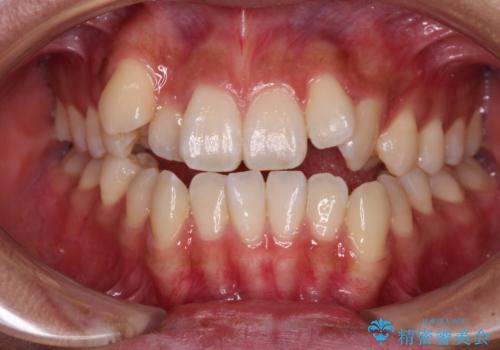

- 前歯の開咬を気にして来院された患者様です。

オープンバイトは舌の突出癖により誘発され、治療後も突出癖が残っている容易に後戻りしてしまいます。

治療期間を短縮するためにも、舌突出癖の改善が極めて重要となります。